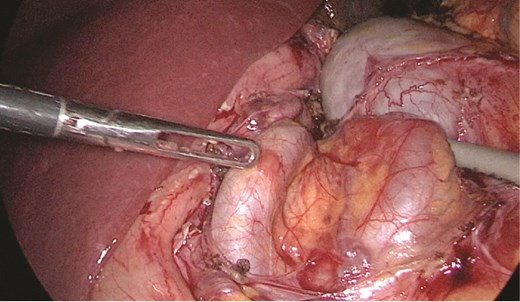

Multidisciplinary discussion was held to evaluate the most appropriate course of action for the patent condition, and the consensus was reached to pursue embolization as a first intervention. Embolization was performed by interventional radiology with no complications post-procedure, and the patient was optimized prior to her procedure. Patient was taken to the operating room in stable conditions. The spleen was enlarged around 20 cm. Inferiorly, the omentum and part of the transverse colon was attached to the spleen (Fig. 3), so we freed the omentum from the splenic tissue. The dissection continued until reaching short gastric vessels and entering the lesser sac (Fig. 4). Once the lesser sac was entered, the splenic vessels were identified (Figs 5 and 6), the splenic vein was hugely dilated with multiple collateral branching vessels at the hilum. Gaining posterior mobilization of the vein was challenging. The splenic artery was tortuous from the insertion around itself (Fig. 7). After complete mobilization of the fundus, we elected to divide each vessel starting with the splenic artery so we can achieve full mobilization of the vein (Fig. 9). After controlling the splenic artery, the splenic vein was dissected proximal to the splenic hilum (Fig. 8). It was hugely dilated and its wall is thickened secondary to AV fistula. It was difficult to achieve circumferential dissection, so we decided at that moment to convert to laparotomy to complete ligating the vein and to retrieve the specimen (Fig. 10a and b).

Anterior portion of the splenic vein seen posterior to the stomach.